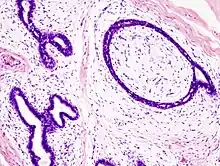

Fibroadenoma of the breast is a benign tumor composed of a biplastic proliferation of both stromal and epithelial components.[14][15] This biplasia can be arranged in two growth patterns: pericanalicular (stromal proliferation around epithelial structures) and intracanalicular (stromal proliferation compressing the epithelial structures into slit-like spaces).

These tumors characteristically display hypovascular stroma compared to malignant neoplasms.[16][17][11] Furthermore, the epithelial proliferation appears in a single terminal ductal unit and describes duct-like spaces surrounded by a fibroblastic stroma. The basement membrane is intact.[18]

Fibroadenoma histology (H&E). The image demonstrates intracanalicular morphology (bottom left) and pericanalicular morphology (top right) -